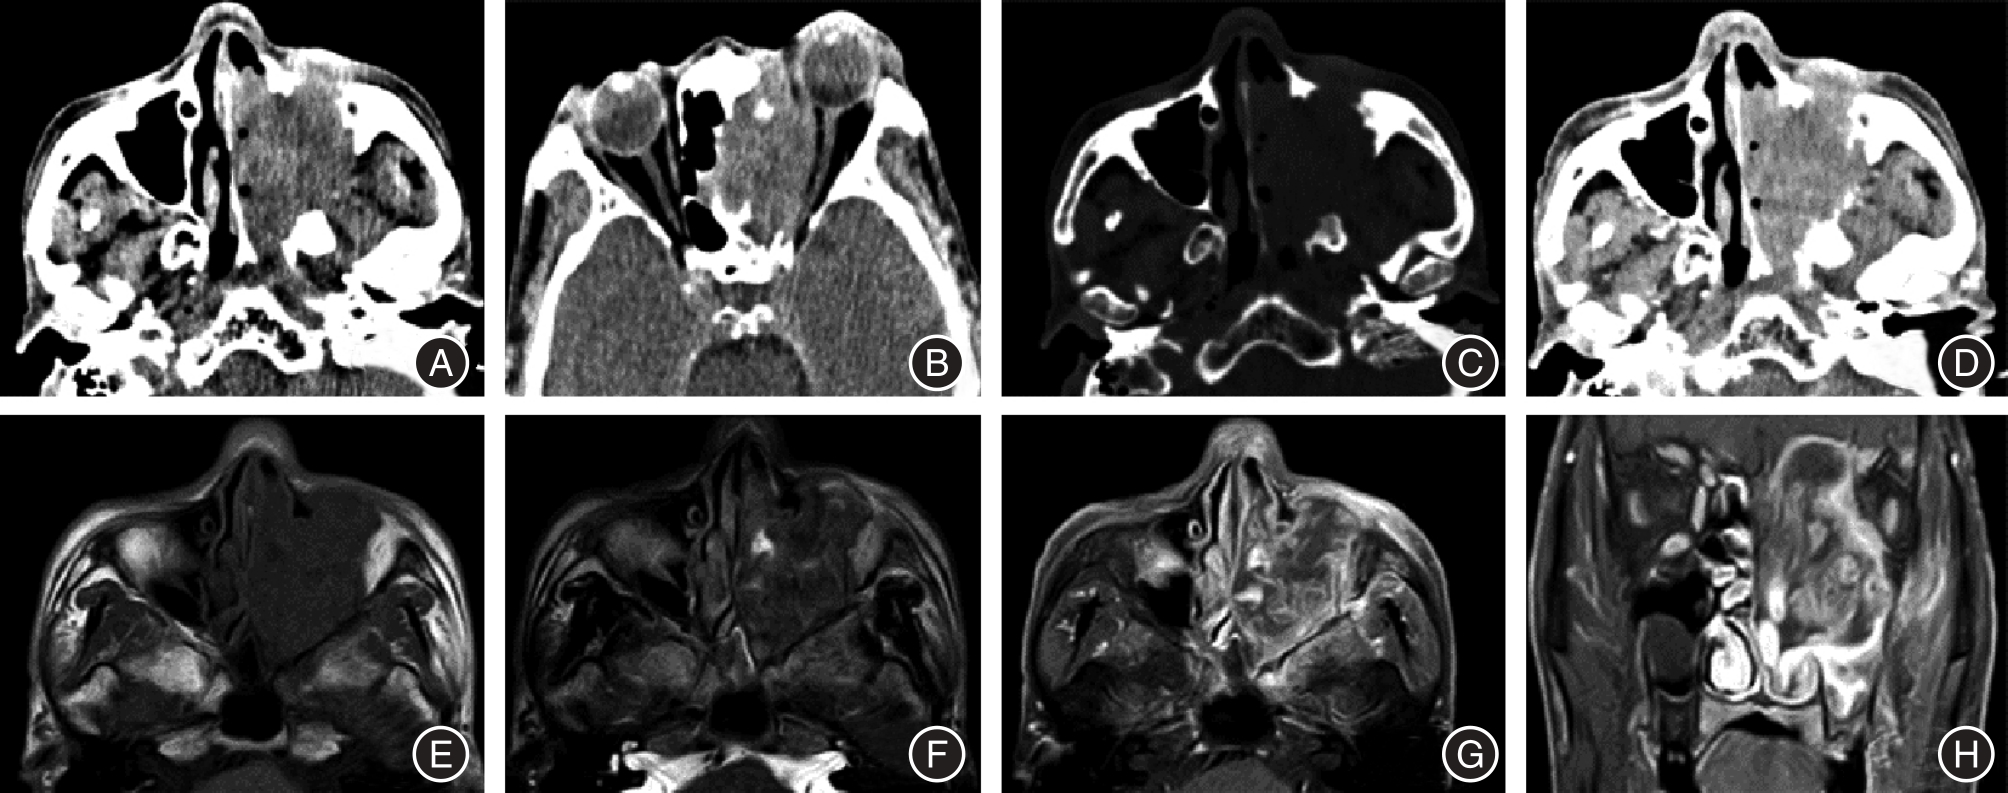

目的 探讨鼻腔鼻窦鳞状细胞癌(SCC)和淋巴瘤(NHL)的增强CT和MRI影像特征,分析不同影像特征鉴别鼻腔鼻窦SCC与NHL的效能。 方法 回顾性分析行鼻窦增强CT和增强MRI检查并经手术病理证实的67例鼻腔鼻窦SCC及NHL患者的影像学及临床、病理资料,分析肿瘤起源部位、最大径、CT密度、MRI信号强度、增强强化程度、肿瘤内部坏死、邻近骨质破坏、对周围组织的侵犯、扫描范围内颈部淋巴结转移情况等影像特征,采用受试者操作特征(ROC)曲线及曲线下面积(AUC)分析不同影像学特征鉴别鼻腔鼻窦SCC和NHL的效能。 结果 鼻腔鼻窦SCC与NHL的肿瘤起源部位、最大径、肿瘤内部坏死、周围骨质破坏以及周围组织侵犯5个影像学特征组间差异有统计学意义(P < 0.05),鉴别SCC与NHL的AUC分别为0.708、0.694、0.785、0.850、0.629。联合肿瘤起源部位、肿瘤内部坏死、周围骨质破坏3个影像特征鉴别SCC与NHL的AUC为0.969,灵敏度及特异度分别为83.9%及97.2%。 结论 肿瘤起源部位、最大径、肿瘤内部坏死、骨质破坏及周围组织侵犯的增强CT及MRI影像征象有助于鼻腔鼻窦SCC与NHL的鉴别,尤其是出现肿瘤起源于鼻腔、坏死少见、骨质破坏轻微,应优先考虑鼻腔鼻窦NHL的可能。增强CT和MRI有助于鼻腔鼻窦SCC与NHL的鉴别,联合使用有助于提高鉴别诊断效能。